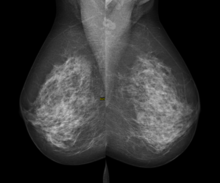

Digital mammography is a specialized form of mammography that uses digital receptors and computers instead of x-ray film to help examine breast tissue for breast cancer.[1] The electrical signals can be read on computer screens, permitting more manipulation of images to theoretically allow radiologists to more clearly view the results.[1][2] Digital mammography may be "spot view", for breast biopsy,[3] or "full field" (FFDM) for screening.[1]

Digital mammography is also utilized in stereotactic biopsy. Breast biopsy may also be performed using a different modality, such as ultrasound or magnetic resonance imaging (MRI).